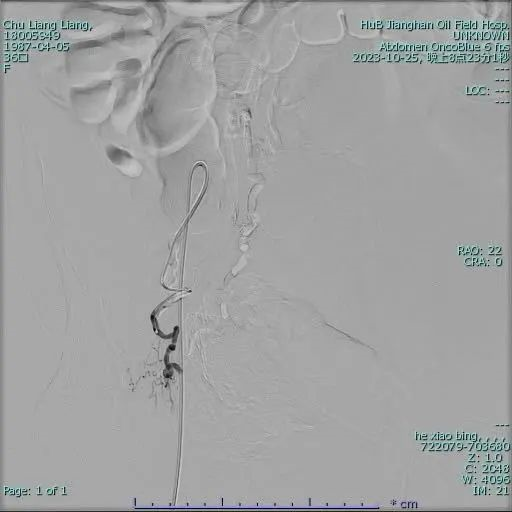

▼左侧子宫动脉栓塞手术前后▼

手术团队已提前准备。在患者推入导管室后,介入放射科主任何小兵通过DSA引导经皮穿刺股动脉将导管置入子宫动脉并释放特殊栓塞材料阻断血供成功实现了止血。

何小兵主任介绍:子宫动脉栓塞术是一种新的微创介入技术。经股动脉穿刺并置入特殊导管,注入栓塞颗粒栓塞住为子宫供血的血管以达到止血的目的,有创伤小、恢复快、并发症少、成功率高的优点。手术中用到的明胶海绵栓塞剂是半永久栓塞剂,会在栓塞血管2-4周后被人体吸收,子宫动脉就会复通,子宫血供可以恢复到栓塞之前。